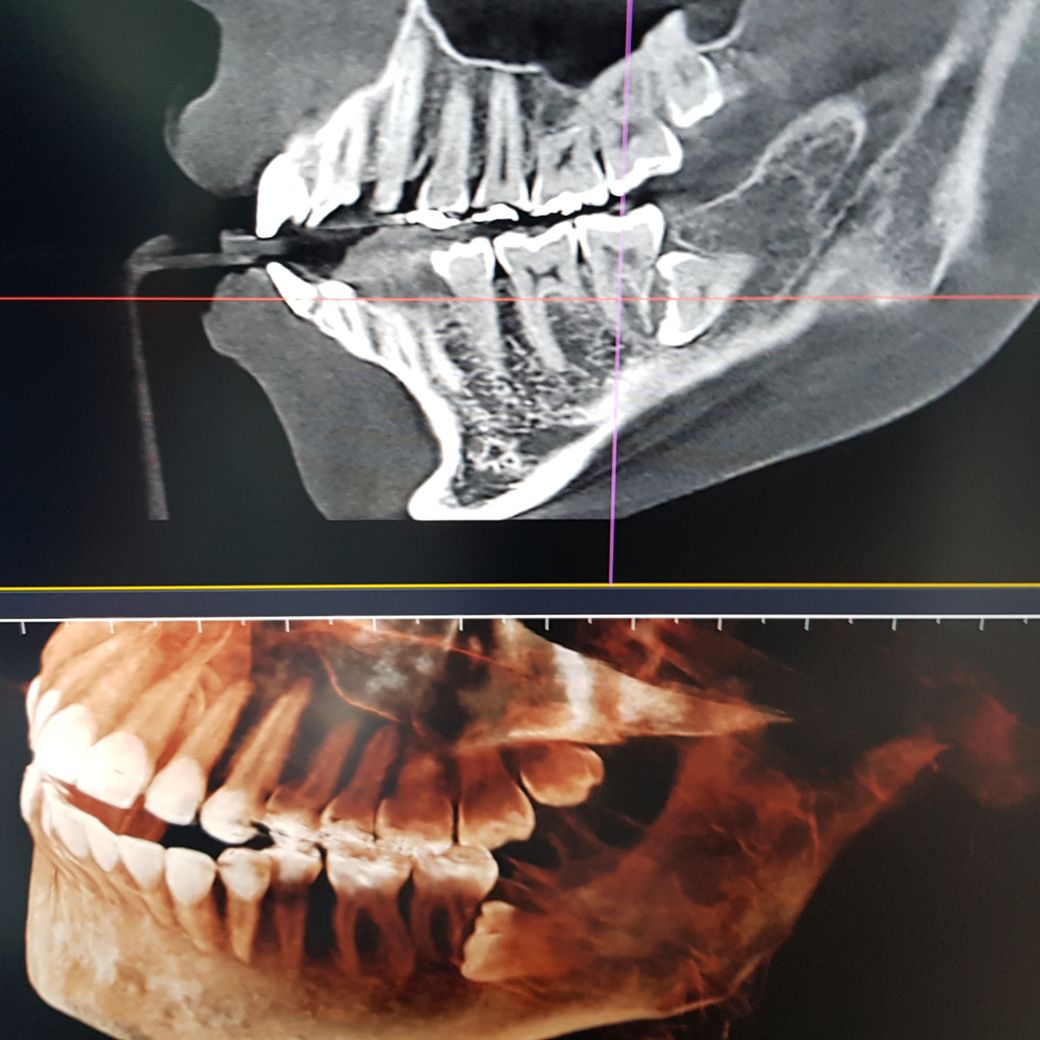

사진과 같이 매복 사랑니 때문에 앞 어금니 뿌리가 먹혔다는 진단을 받아서 둘 다 한꺼번에 발치할 예정입니다. 아무래도 임플란트를 하는 수밖에 없을까요? 혹시 다른 방법이 있을지 궁금해서 여쭤봅니다.

• 1번 째 사진

• 2번 째 사진

• 3번 째 사진